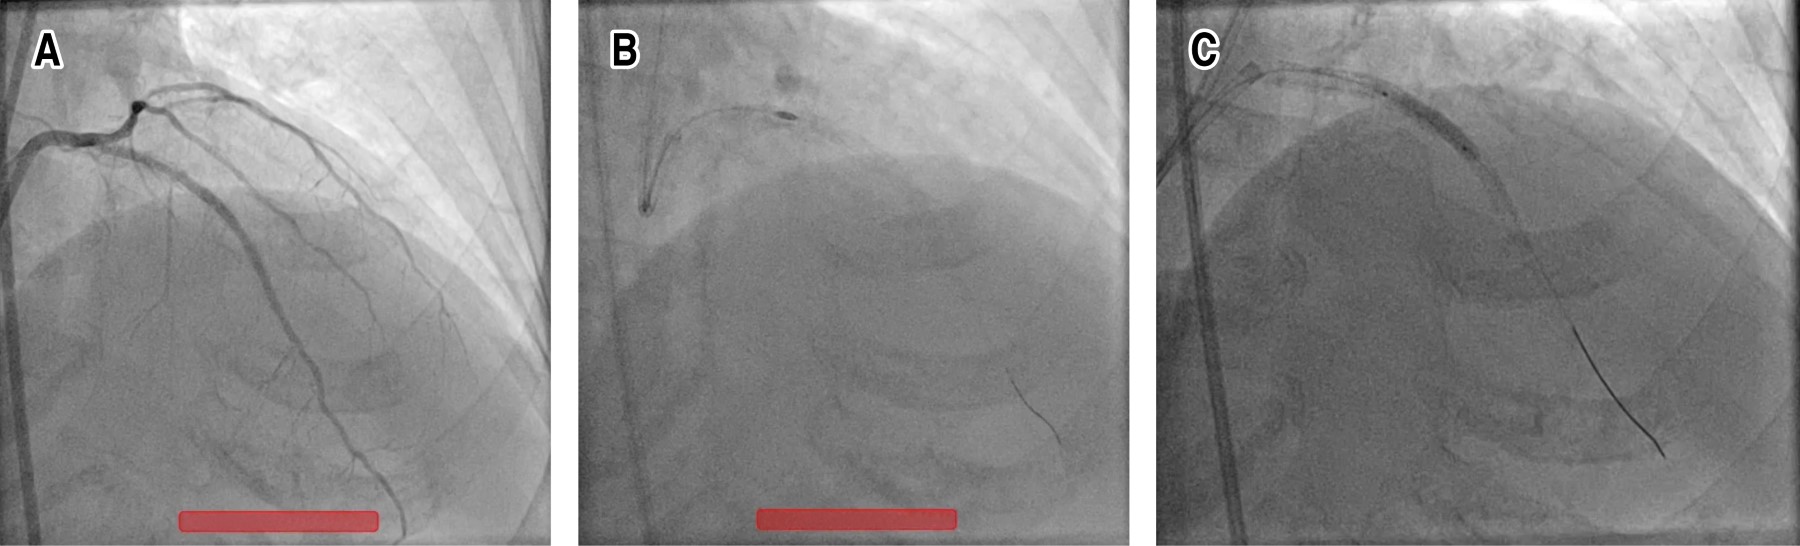

La subexpansión es una cuestión importante para los cardiólogos intervencionistas en términos de resultados a largo plazo. En este documento informamos una rotación exitosa de puntales de stent subutilizados. Mujer de 75 años con antecedentes de Intervención Coronaria Percutánea (ICP) sobre Arteria Descendente Anterior (ADA) izquierda con dos stents farmacoactivos superpuestos hace una semana en otro centro. Desafortunadamente los stents se desplegaron sin una preparación adecuada de la lesión en lesiones muy calcificadas y por lo tanto, no se pudieron dilatar adecuadamente después del despliegue. Los struts de la endoprótesis se rotaablizaron con éxito con fresas de 1.5 y 1.75 respectivamente y a continuación se implantó la endoprótesis. El paciente fue dado de alta sin incidentes. La expansión insuficiente de un stent generalmente se debe a una preparación inadecuada de la lesión. El deterioro de la cicatrización secundario a puntales del stent poco expandidos es la principal causa de reestenosis a corto plazo. Por lo tanto, es de gran importancia una predilatación adecuada, especialmente en lesiones muy calcificadas. Se deben utilizar técnicas más sofisticadas como balón Non-Compliant Balloon (OPN), rotablación, balón de ondas de choque y láser para una predilatación adecuada cuando los métodos convencionales de predilatación con balón fallan. Estos métodos también se pueden utilizar para la dilatación de un stent poco expandido. En consecuencia, la expansión insuficiente de un stent es una de las principales causas de reestenosis del stent. La rotaablación se puede utilizar para reducir el tamaño de los puntales del stent poco expandidos y por lo tanto, prevenir una posible reestenosis a corto plazo.

Figura 1